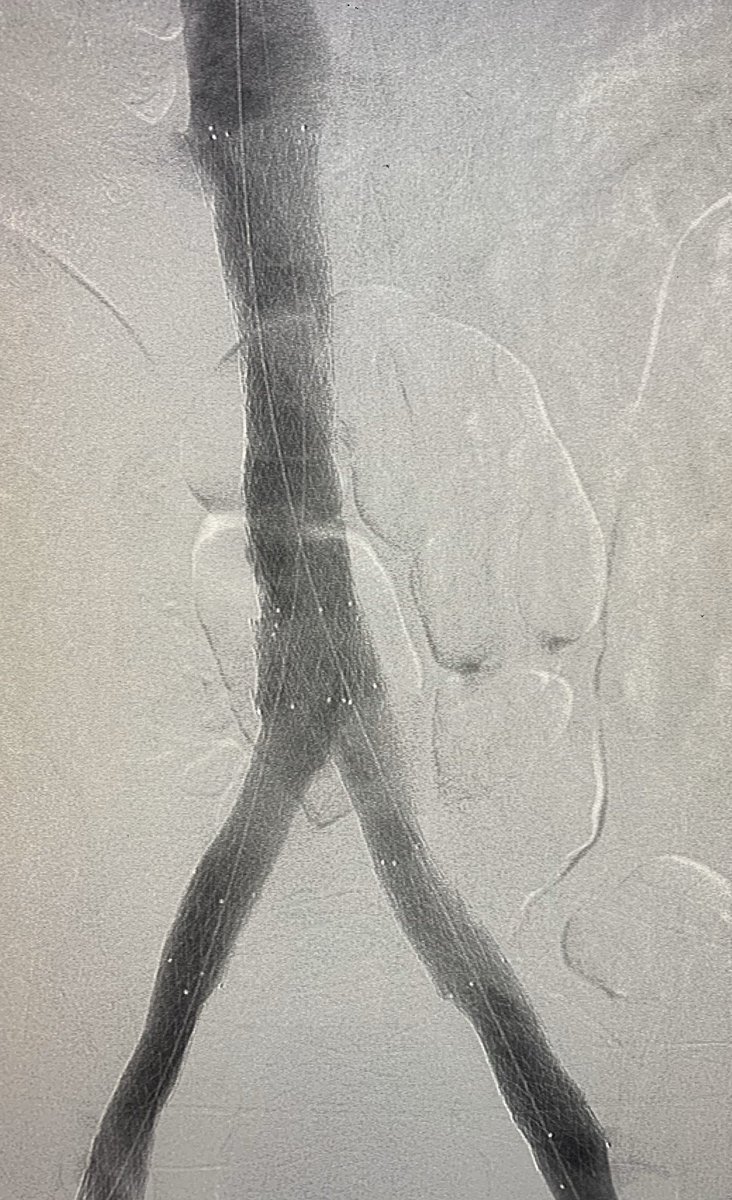

#venousreconstruction for b/l#legswelling.#IVC#occlusion from#filter placed 6 months ago for DVT and brain bleed. 2 IR effort ( Dr. Gordon).#filterretrieval followed by#iliocaval#stenting with#venovo.#irad#twittIR@SIRspecialists@SIR_ECS@SIRRFS@JVIRmedia@PairsWebpic.twitter.com/PqlCM1BJxL